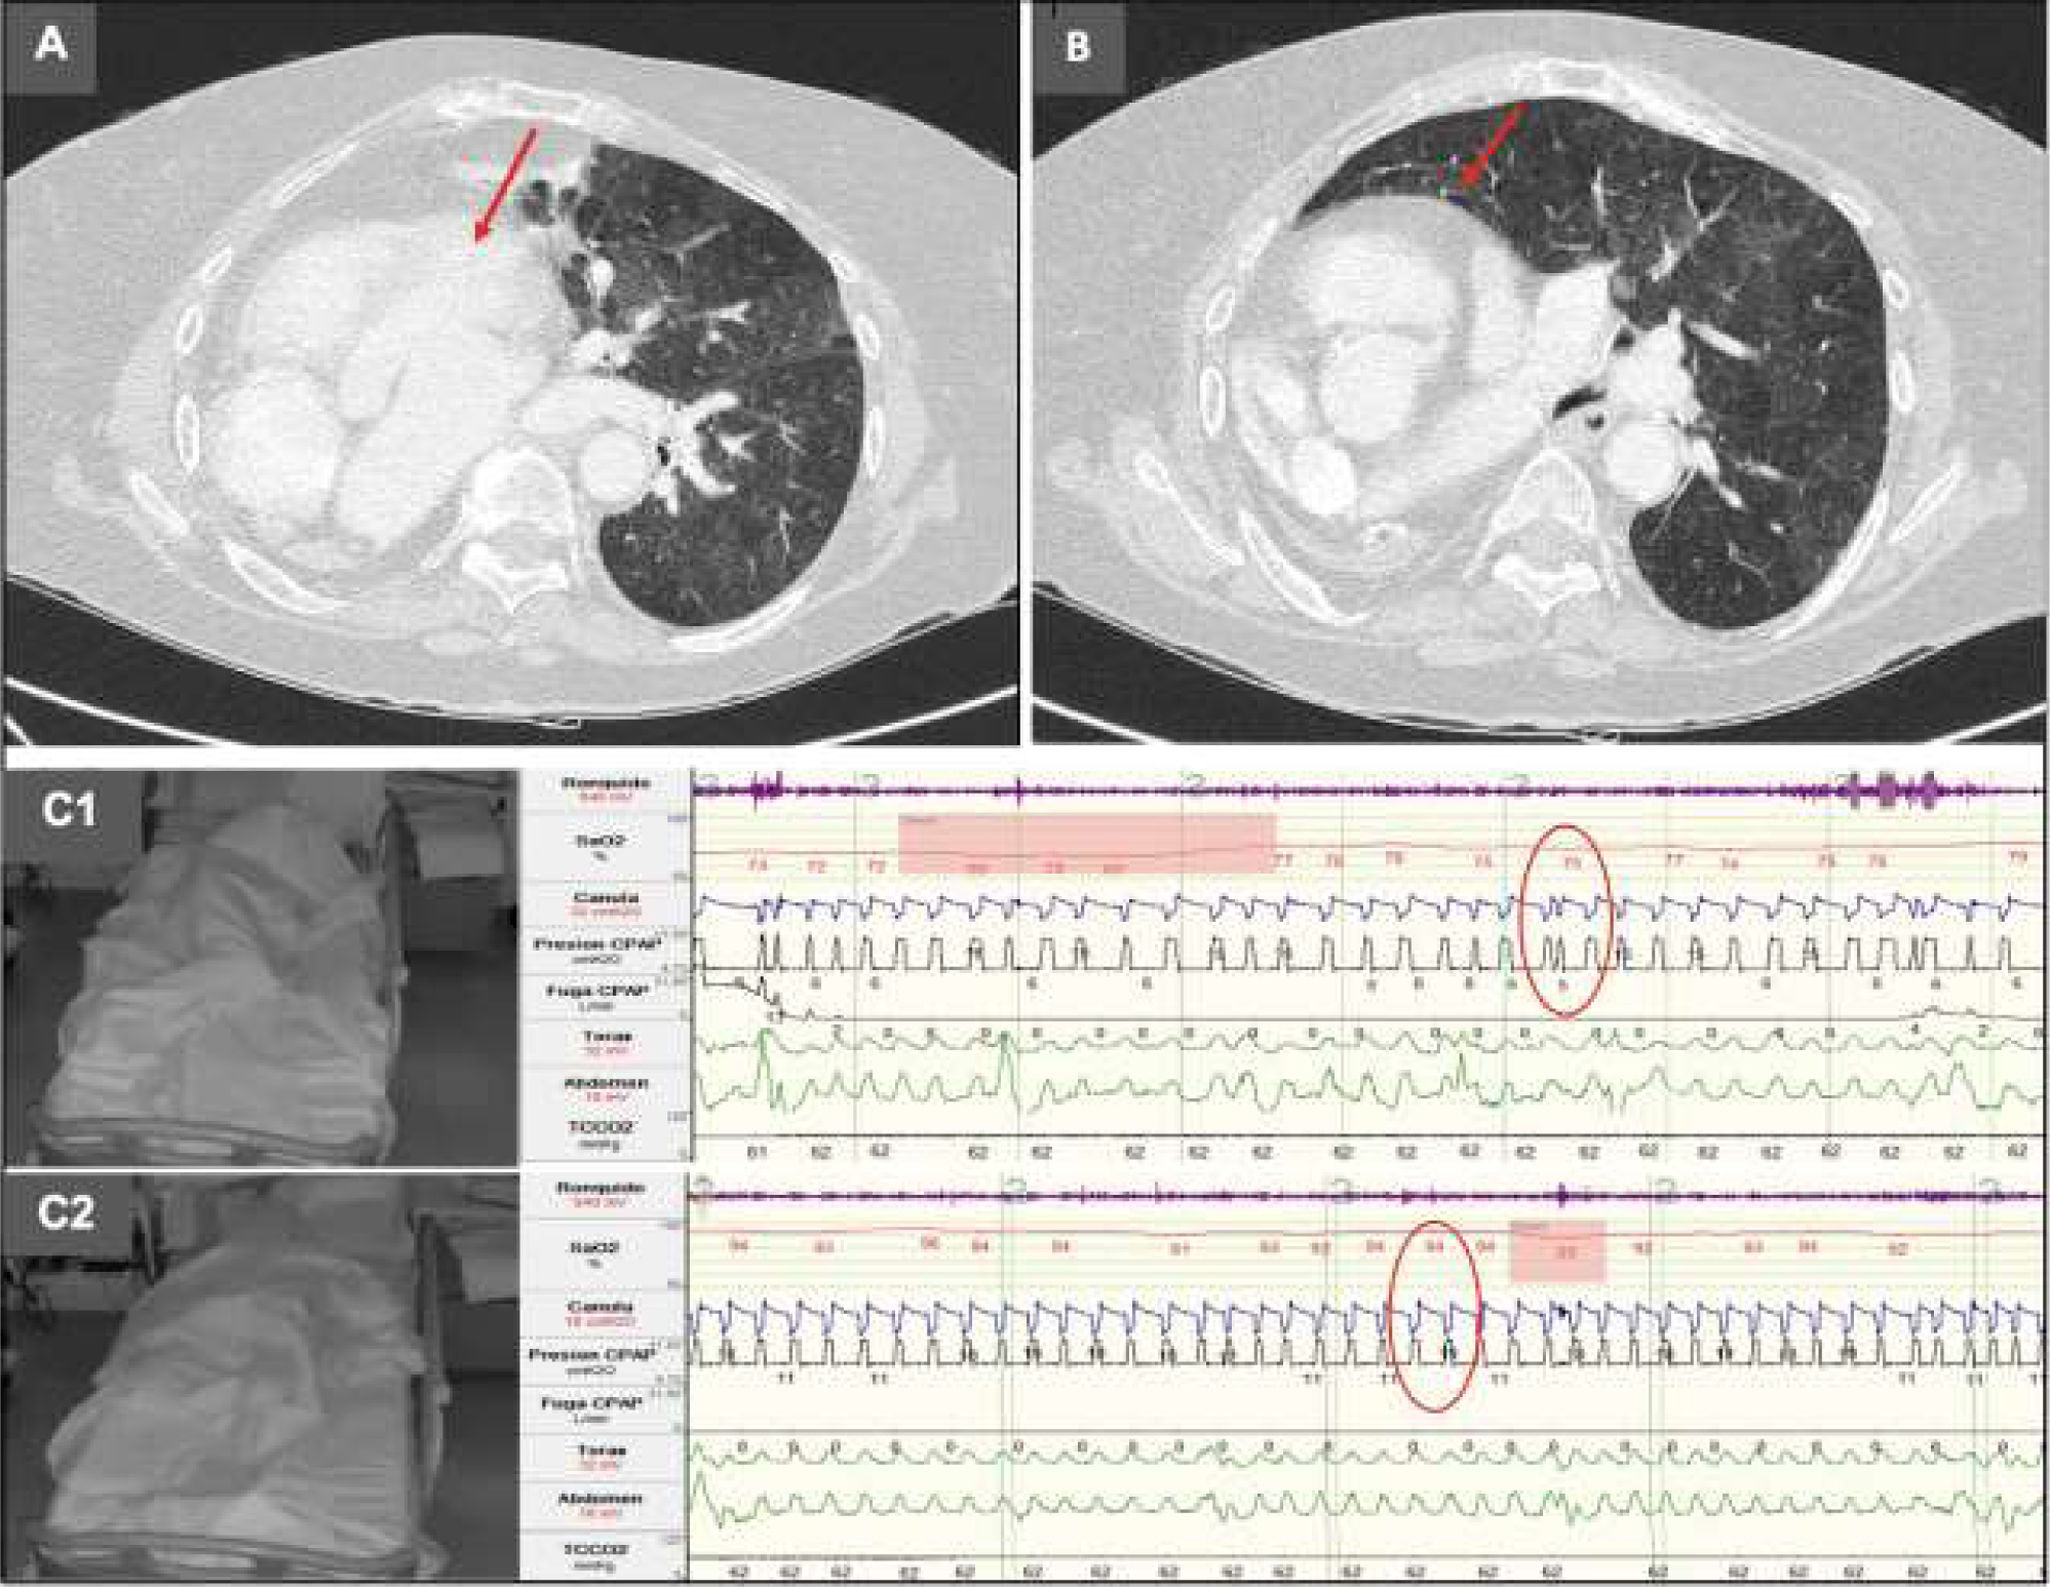

Pulmonary hypoplasia and congenital dextrocardia presenting with hypercapnia in advanced age